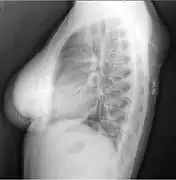

X-ray of a lipoma

X-ray showing lipoma